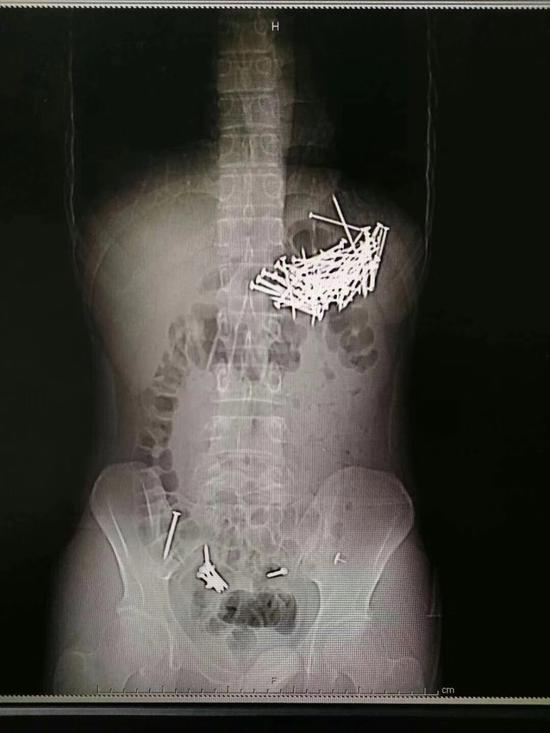

小伙肚中被取出87根铁钉 自称吃了“钉子馅”包子

法制晚报·看法新闻(记者 董振杰 通讯员 唐静霞)8月10日早上,湖南郴州第一人民医院内,腹疼难忍就医后被医生从体内取出87根铁钉的小伙子终于醒了过来。守护在重症监护室内的医护人员松了一口气。

小伙子体内被发现大量钉子 医院供图

8月8日晚上,湖南省郴州市第一人民医院接到求救信息,一个在北湖路某酒店居住的小伙子称自己吃了包子后肚子疼痛难忍,需要医生急救。120急救人员将其接到医院后发现,小伙子所吃的包子馅有异常。“拍片之后可以看到,他的肚子内有大量钉子状物体。”郴州市第一人民医院一名值班医护人员表示,在手术之前,小伙子交给医生一封写给女友的“遗书”,说是若找不到亲属,可以打电话给女友。

8月9日晚上7时许,联系到小伙子的亲属之后,医院制定了手术方案并取得家属同意,经过4个小时的忙碌,医生从小伙子的腹腔和胃部等取出共87根铁钉,每根钉子大约四五厘米长。“见过吞食异物的病人,但是没有见过吞下这么多钉子的病人。”一名医护人员表示,小伙子自称是吃了“钉子馅”包子,“肯定是一时想不开,才做了傻事,这可忙坏了我们连夜做手术的医生,醒来之后我们得好好劝劝他。”

据手术医生胡志辉介绍,经过检查和手术证实,这个小伙子吞食了87根铁钉和7枚图钉,其中6枚图钉被病人自行排出,目前余下一枚图钉在直肠附近,由于体积较小,病人应该可以自行排出。